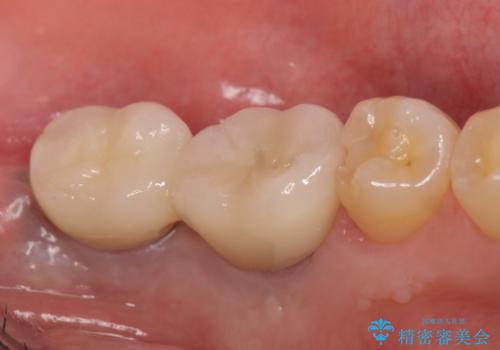

- 数年前に左下の奥歯を2本失ってから物が咬めないため何とかして欲しいと当院にいらっしゃった方の症例です。

左下にインプラント(ストローマン)を2本埋入し、オールセラミッククラウンによる補綴を行いました。

今回用いたオールセラミッククラウンはジルコニアフレームという白い素材の上にセラミックを盛っているため、審美性が非常に高いのが特徴です。

また、ジルコニアは人工ダイヤモンドの材料にも使われているほど高い強度を持っており、そのためオールセラミッククラウンは審美性だけでなく、奥歯やブリッジの補綴も可能とするクラウンです。